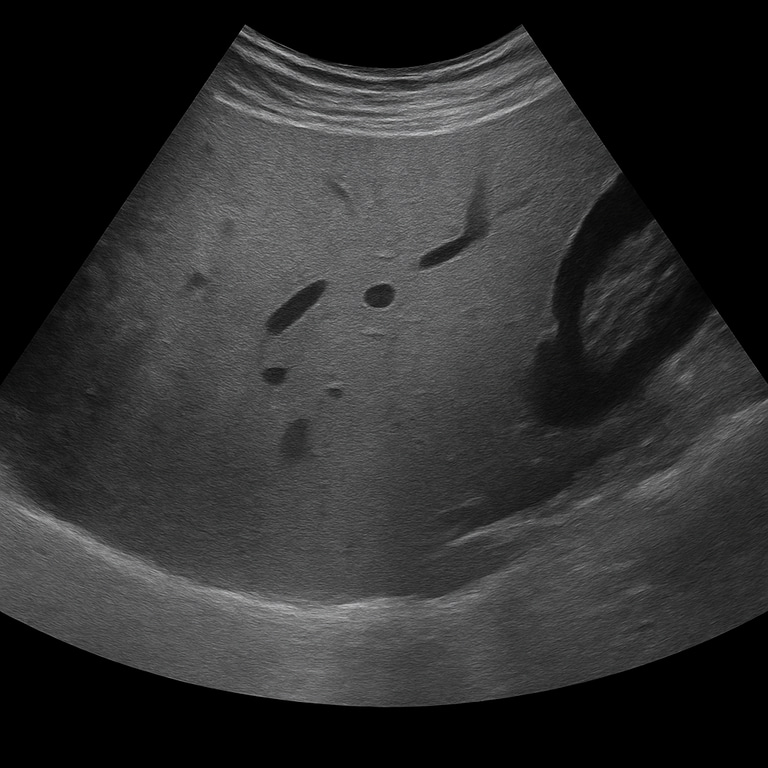

Ultrasound examination of the liver is used to examine the size, structure and vascular flow of the liver. The examination is performed by specialist radiologists and provides detailed images in real time that show changes that may indicate fatty liver, inflammation, cysts, tumors or cirrhosis. Ultrasound of the liver is often the first-line method for investigating abnormal liver tests or abdominal complaints related to the liver.

Unlike MRI or CT, which are used for detailed mapping of tissue changes and blood vessels, ultrasound is the primary method for assessing liver structure, fat deposition, vascular flow, and volume. Ultrasound can quickly detect abnormalities without radiation and is often used as the first step in liver diagnostics.

The examination is performed while you lie on your back or slightly on your left side. A gel is applied to the skin and the doctor moves the ultrasound probe over the area under the right rib cage. The examination usually takes 15–20 minutes. For the best image quality, you should fast for about 4–6 hours beforehand, as food and air in the intestine can affect the clarity of the image.